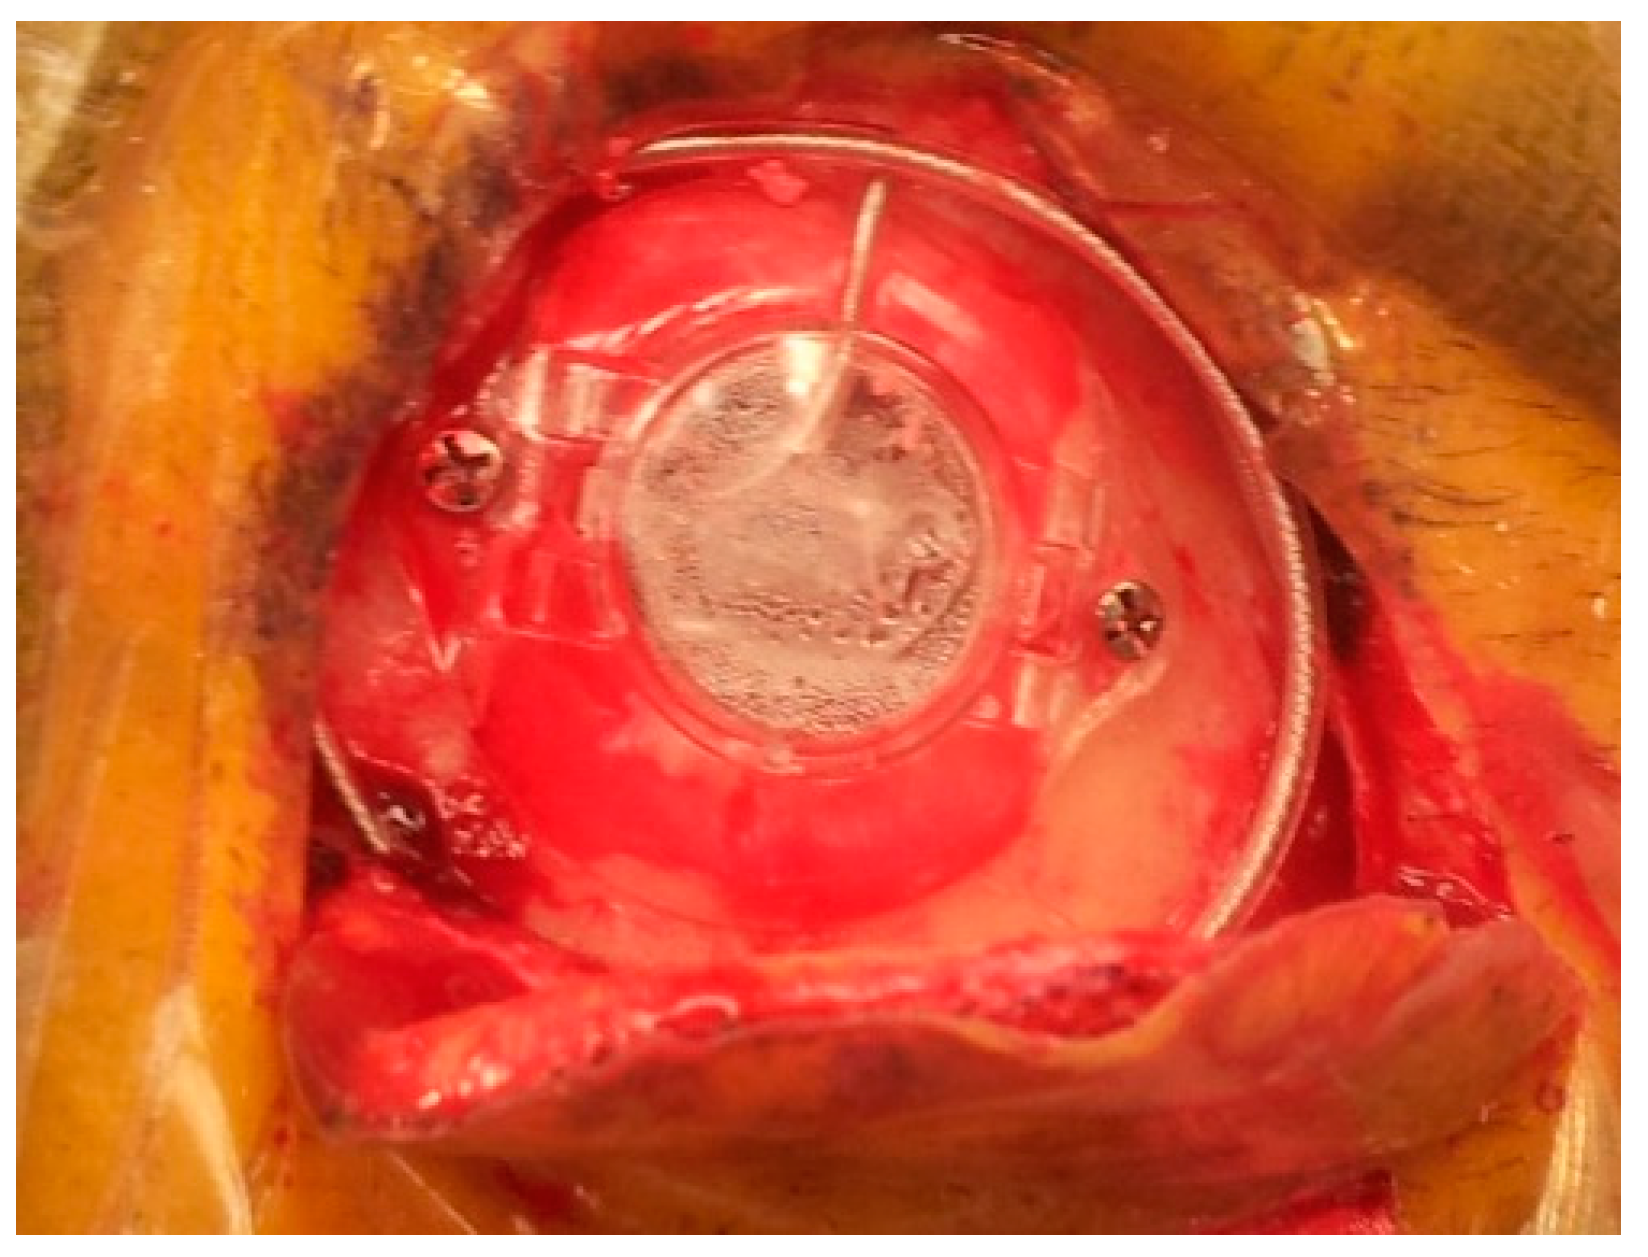

Figure 13. The final appearance of the electrode fixed using the Stimloc device; the excess of the electrode is coiled around the burr hole to create a strain relief loop.

After identification of the STN borders and depth by the MER, we started high-frequency macrostimulation. The aim of the stimulation was to confirm the optimal target, which provided adequate control of the Parkinsonian symptoms (specifically tremors), without undesirable effects from stimulation below 4 volts. Once we reached our desired target, we removed the microelectrode and replaced it with a standard four-contact (0–3) deep brain stimulation electrode (Medtronic DBS lead 3389). Generally, we placed the deepest electrode contact (0) at or just beyond the target point. We repeated the testing using this electrode in order to confirm the reproducibility of the effects. We locked the electrode in place using a Stimloc device (Medtronic, Minneapolis, MN, USA) (Figure 12). The excess of the electrode was coiled around the burr hole to create a strain relief loop (Figure 13). Then the same procedure was repeated on the right side.